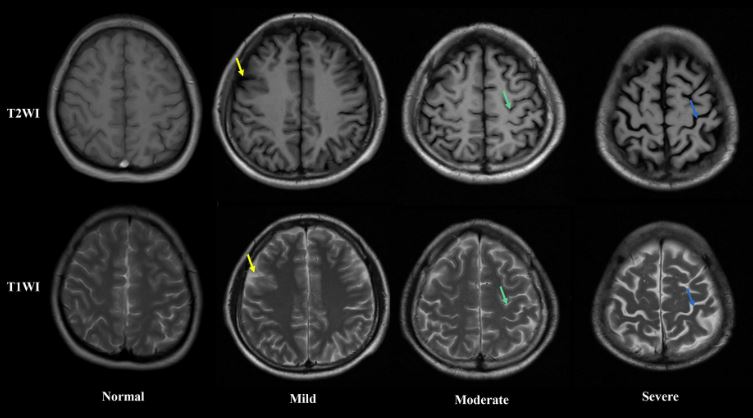

Οι 88 συμμετέχοντες με AUD που συμμετείχαν στη μελέτη έκαναν μαγνητικές τομογραφίες στη μία εβδομάδα, στον ένα μήνα και στους 7.3 μήνες της αποχής τους από το αλκοόλ. Μόνο 40 από τους 88 κατάφεραν να απέχουν από το αλκοόλ για την πλήρη περίοδο της έρευνας. Για χάρη σύγκρισης, οι ερευνητές έκαναν μαγνητικές τομογραφίες και σε 45 ανθρώπους που δεν είχαν ποτέ AUD, μία φορά με την έναρξη του πειράματος και μία εννέα μήνες μετά για να επιβεβαιώσουν πως οι περιοχές που μελετούσαν παρέμειναν ίδιες.

Συνολικά οι ερευνητές κατέγραψαν το πάχος του φλοιού σε 34 περιοχές του εγκεφάλου και στα δύο ημισφαίρια. Μετά τους 7.3 μήνες χωρίς αλκοόλ, η διαφορά ήταν στατιστικά σημαντική στις 25 από τις 34 περιοχές, ενώ στις 24 από αυτές έφταναν το επίπεδο ανθρώπων που δεν έκαναν κατάχρηση αλκοόλ.